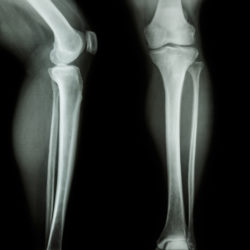

film x-ray leg & knee AP(Anterior-Posterior)/lateralMore and more patients are filing reports and lawsuits over Zimmer persona knee complications, alleging their knee implant devices were defective. The manufacturer issued a recall over these Zimmer persona knee complications in 2015. Patients say they have suffered from Zimmer persona knee complications after implantation with one of these devices between 2012 and 2015.

Unfortunately, the tibial plate component was linked with device loosening. A loose device can allow it to move, leading to gaps between the knee implant and bone visible in X-rays. Loosening of a knee implant can lead to further Zimmer persona knee complications and can cause serious damage.

• Radiolucent lines

There are two main Zimmer persona knee complications that patients report. The first of these Zimmer persona knee complications is radiolucent lines, which are small gaps between the knee implant and the bone. The second major complication is device loosening.